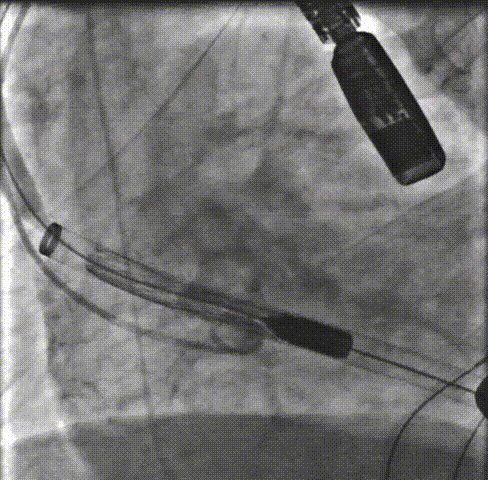

患者术后即刻食道超声和造影可见支架位置固定良好,支架扩张形态均匀一致,瓣叶启闭运动好。植入主动面瓣膜最大峰值血流速为1.4m/s,平均跨瓣压差为8mmHg,瓣口面积约为2.4cm²,支架内未见明显反流,瓣架前后缘轻度瓣周漏。

术后第4天超声提示人工支架瓣膜位置良好,无移位,瓣膜活动度佳。舒张期主动脉瓣周微量反流。